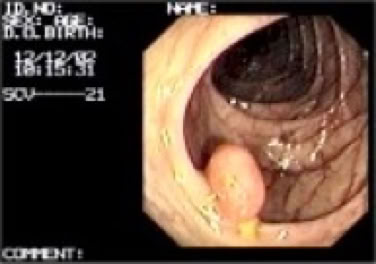

>>   Polypektomie

Detektion und Abtragung von Polypen ist einer der Hauptziele der Coloskopie (präventativ oder kurativ).

Die Abtragung erfolgt mit der Schlinge, bis 8 mm „kalt“, ab 8 mm „heiß“. Limit sind ungünstige Polypenlage (z.B. breitbasig im Coecum) sowie kräftige Polypenstiele (Gefahr der arteriellen Blutung). Durch Verwendung des Erbe HF-Erbotoms ICC 200 Autocut wird das Blutungs- und Perforationsrisiko erheblich gesenkt ( Blutungsstillung ).